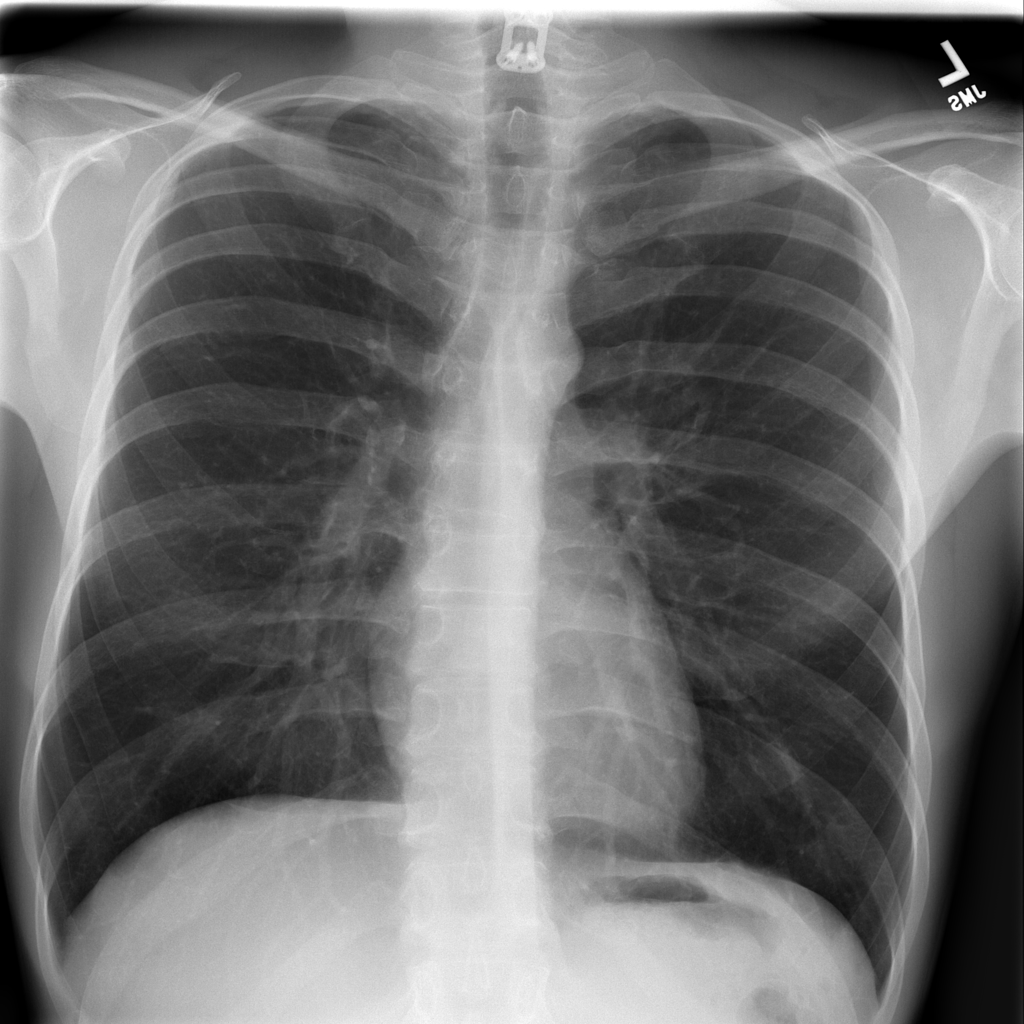

Trained a DenseNet121 Deep learning architecture on a Dataset of 112,120 frontal-view X-rays. The network was configured in PyTorch Python and trained on a Rutgers University GPU Cluster . The Web Dev is done in Django python to create a platform for professionals to share it with others.

An amazing average accuracy of 85.0846 on the test set trained on a 121 layer Dense CNN.